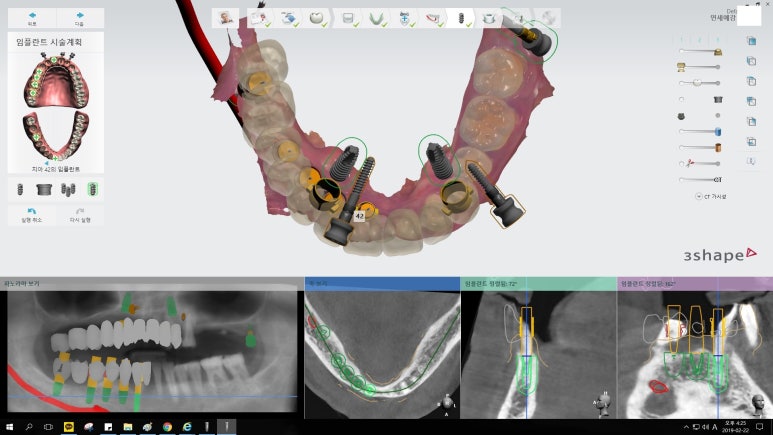

오늘은 임플란트, 조금 더 안아프고 간편하게 할 수 있는 방법에 대해

실제 저희 치과에서 진행한 사례를 통해 알아보고자 합니다.

50대의 나이에도 남은 이가 거의 없는 분입니다.

이러한 세세한 시뮬레이션, ct를 이용한 컴퓨터 분석을 통해

더 정확하고 안전하게 적절한 위치에 임플란트를 식립할 수 있었으며

절개가 없는 비절개 방식을 이용한 인플란트로

수술시간이 짧고 실밥을 풀 필요가 없으며, 환자분의 만족도도 높습니다.